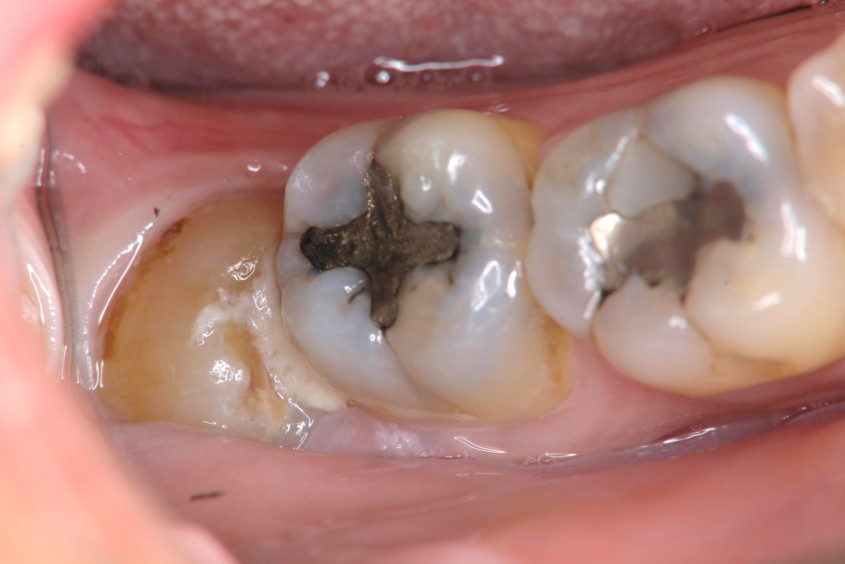

1週後傷口癒合良好

術前、術後比較